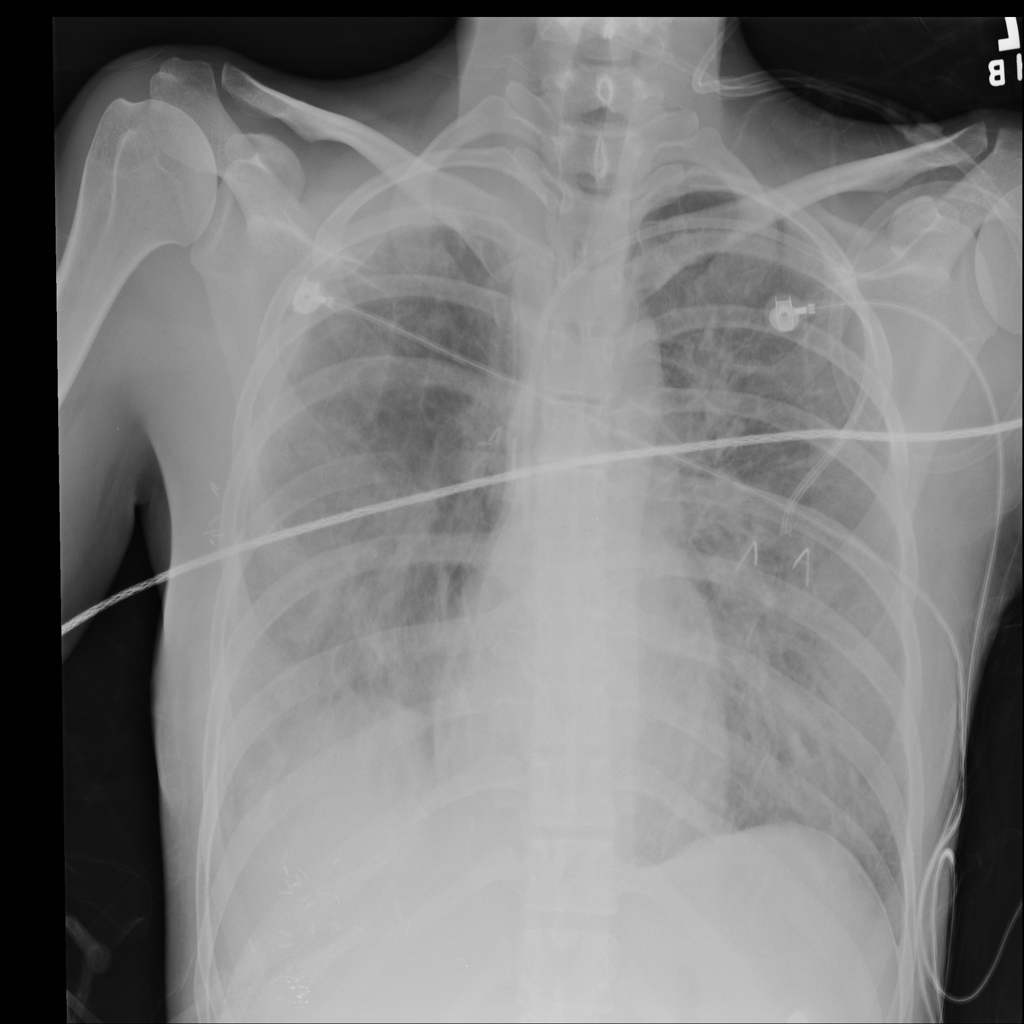

PAT-E828 · IMG-004Edema

PAT-E828 · IMG-004

AP